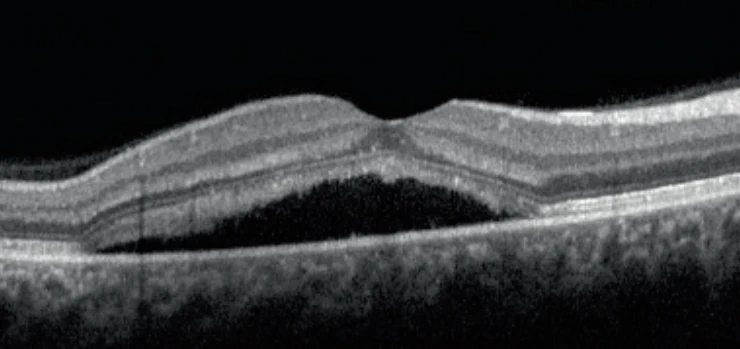

Retinopathie centralis serosa (RCS) of chorioretinopathie centralis serosa (CCS) is een ophoping van vocht onder de zintuigcellenlaag van het netvlies. De oorzaken en mechanismen worden momenteel niet volledig begrepen, maar men vermoedt een gestoorde pompfunctie van het pigmentepitheel (RPE) onder de zintuiglijke cellen, die wordt veroorzaakt door een zwelling en overmatige permeabiliteit van de choroïdale vaten onder het getroffen gebied.

Typische symptomen zijn frequent eenzijdig verlies van gezichtsscherpte, het optreden van metamorfopsie (vervormd zicht) en de waarneming van groenachtige of grijsachtige vlekken in het gezichtsveld.